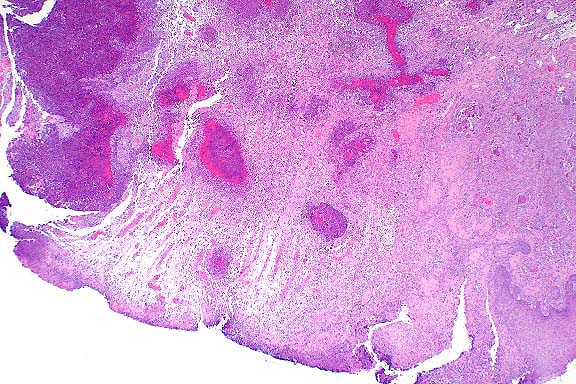

- Kidney, hematoxylin and eosin stained sections.

- Multifocally, proximal renal tubules have swollen and vacuolated

epithelial cells. Affected epithelial cells contain variably-sized,

intracytoplasmic, eosinophilic, granular deposits and low numbers

of eosinophilic, hyaline droplets and crystals.

40x

obj

- Case 12-4. Kidney. The cytoplasm of many proximal

tubules is rarified, somewhat foamy, and often contains globular

to to polygon shaped eosinophilic inclusions.

- Transmission Electron Micrograph, 1540X. Kidney, proximal

tubules. The electron micrograph illustrates portions of four

proximal tubules lined by tall cuboidal epithelial cells with

a brush border, oval nuclei with dispersed chromatin and 1-2

small nucleoli, and abundant mitochondria, many arrayed perpendicularly

to the basement membrane. The epithelial cells are swollen, vacuolated,

and have numerous, intracytoplasmic osmiophilic amorphous deposits

(secondary lysosomal contents) surrounded by an electron-lucent

space and a single membrane (fused lysosomes) and large, rectangular,

rhomboid or irregular to needle-like crystalline intralysosomal

deposits (alpha 2m globulin). Interspersed between the proximal

tubules (lower left) are small spindle cells with oval nuclei

(mesangial cells).

- This case is an example of two lesions, both lysosomal. The

crystalline deposits are due to deposition of alpha 2m globulin,

while the fused or coalesced secondary lysosomes distended with

amorphous material are consistent with a lysosomal storage disorder.

- Alpha 2m globulin deposits may be globular, rectangular,

rhomboid or irregular in shape. Alpha 2m globulin is produced

in large quantities in the liver of male rats, and accumulates

as hyaline droplets in the renal tubular epithelium. Numerous

chemicals can disrupt the metabolism of alpha 2m globulin, resulting

in an exacerbation of protein deposition and more rapid development

of nephropathy due to tubular degeneration and necrosis.

- The other lysosomal alterations are consistent with a lysosomal

storage disorder, in this case due to cyclodextrin administration.

Cyclodextrins are widely used in oral, topical and parenteral

pharmaceutical preparations to increase solubility and form stable

complexes that result in enhanced drug delivery. Toxicity with

these compounds varies with the specific type of cyclodextrin.

Renal lesions, specifically proximal tubular degeneration and

necrosis, are associated with methylated cyclodextrins, particularly

TM-beta-cyclodextrins. Although the exact mechanism for the tubular

lesion is unknown, these compounds disrupt phagosomal-lysosomal

fusion. Although acicular microcrystals have been reported with

some cyclodextrins, their origin and significance have not been

determined. In the case presented here, crystals were consistent

with alpha 2m globulin.